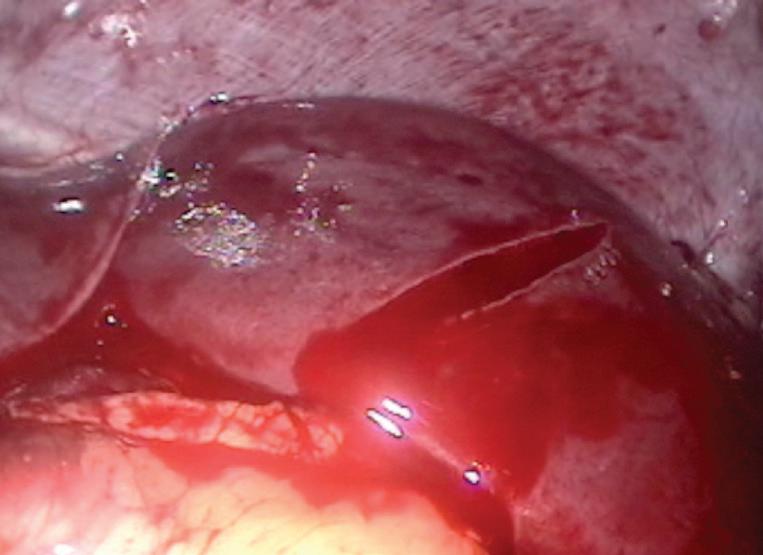

инвазивна апаратна вентилация. Изяви се синдром на

остър хирургичен

корем с наличие -

то на балониран ко -

рем, вяла до липс -

ваща перисталтика,

липса на дефекация след раждането. От

проведените образ -

ни изследвания и

консултация с детски хирург се установява чревна непроходимост. Предприе се оперативно лечение, като интраоперативно

рационна пневмония, анемичен синдром, токсично увреждане на черния дроб с холестаза, кахексия, синдром на късото тънко черво. По-късно е насочена към друго лечебно заведение за последващо лечение.